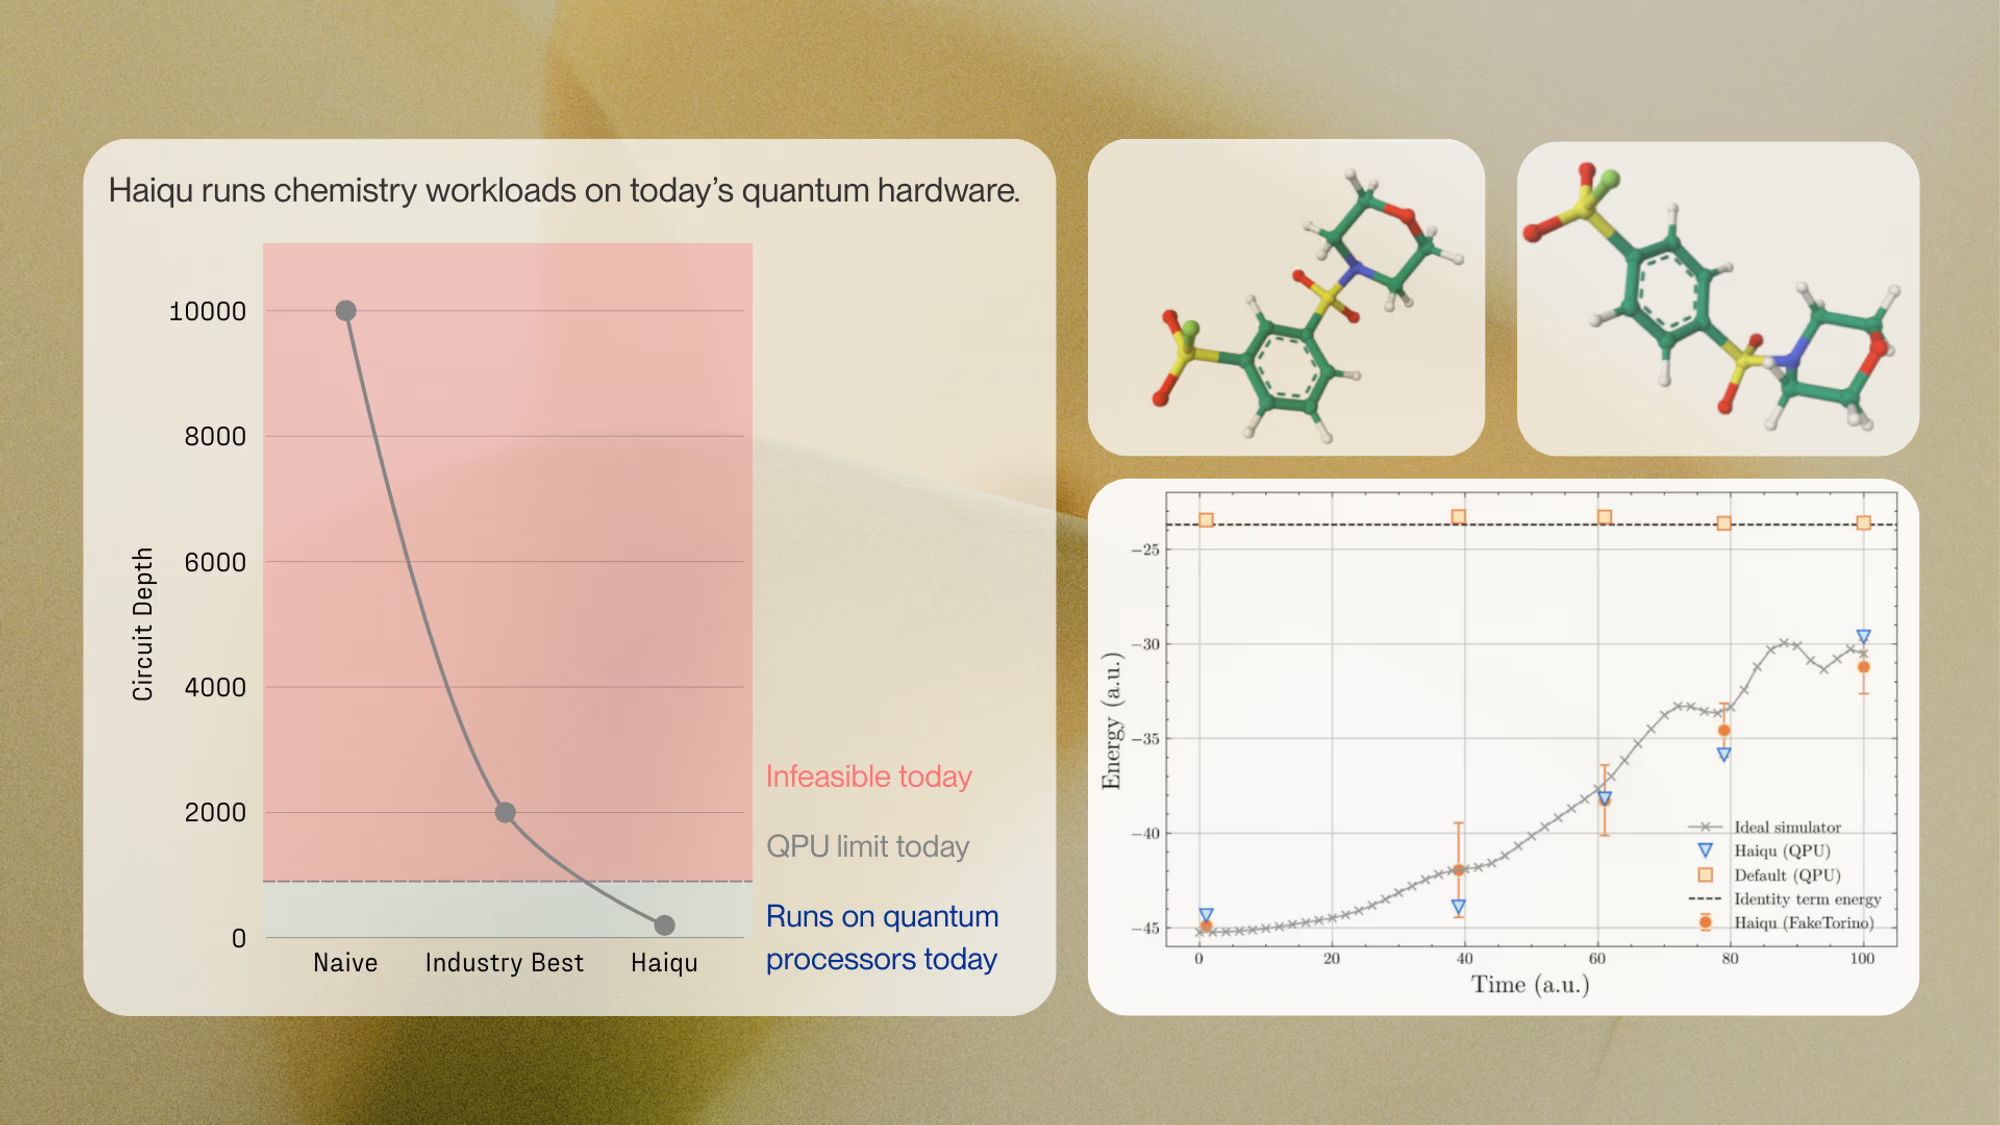

Problem: Quantum chemistry workloads exceed today’s hardware limits in circuit depth, noise, and cost.

Quantum computing offers a solution, but until now has been constrained by hardware noise, limiting usable circuit depth to a few hundred two-qubit gates. Haiqu, working with Capgemini, IBM, and GSK, broke this barrier by demonstrating one of the largest electronic-structure Hamiltonian simulations ever run on real quantum hardware for covalent drug warheads. Using advanced circuit compression and middleware execution, the team initially reduced circuit depth by 15.5× and further allowed end-to-end execution by running sub-circuits up to 371 gates.

Solution: Decomposed prohibitive quantum runs into hardware-friendly, separable blocks.

Collectively, these results establish a scalable, hardware-realistic path for running Hamiltonian simulations on larger active spaces, while maintaining sufficient accuracy for molecular reactivity prediction.